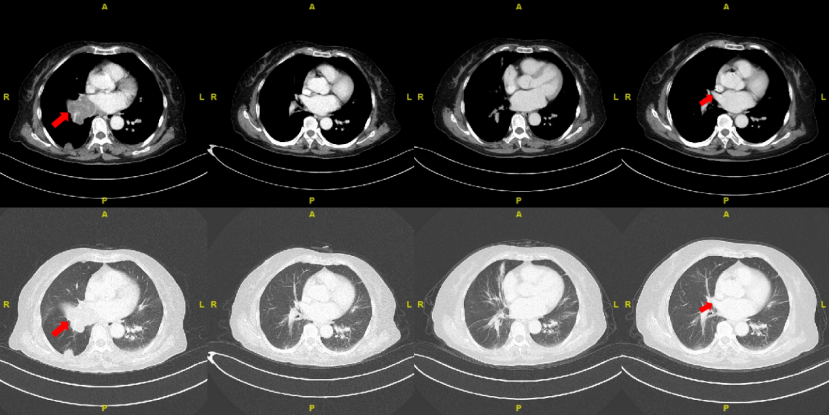

image.png

原发灶胸部CT结果对比图(基线、2周期后、4周期后、6周期后)